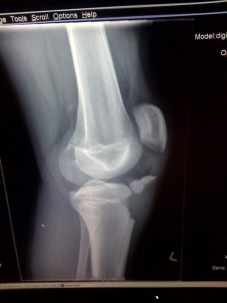

Veľmi zlá správa prišla dnes pre náš reprezentačný tím z poza mora. Najmladší člen širšieho reprezentačného tímu pre majstrovstvá sveta Noah Hoselton si počas zápasu proti Carletonskej univerzite v jednom zo súbojov zlomil nohu a jeho účasť na MS je ohrozená. Podľa slov lekárov bude Noko ako ho všetci na Slovensku familiárne voláme, musieť pauzovať tri mesiace a ďalšie tri mesiace si vyžiada rehabilitácia.